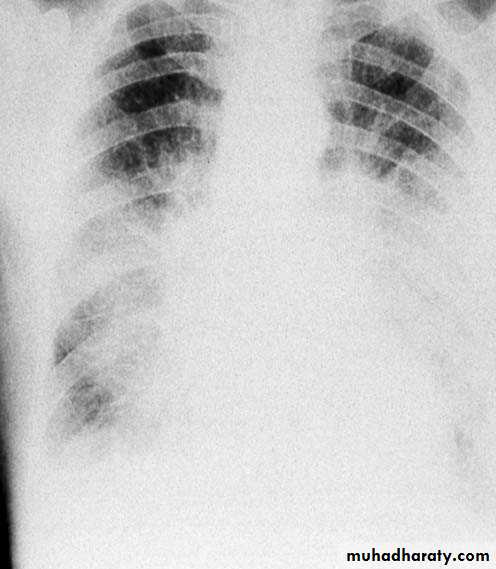

Patients with HF complain of dyspnea, orthopnea, paroxysmal nocturnal dyspnea, fatigue, and dependent edema.

Diuretics relieve pulmonary congestion and peripheral edema